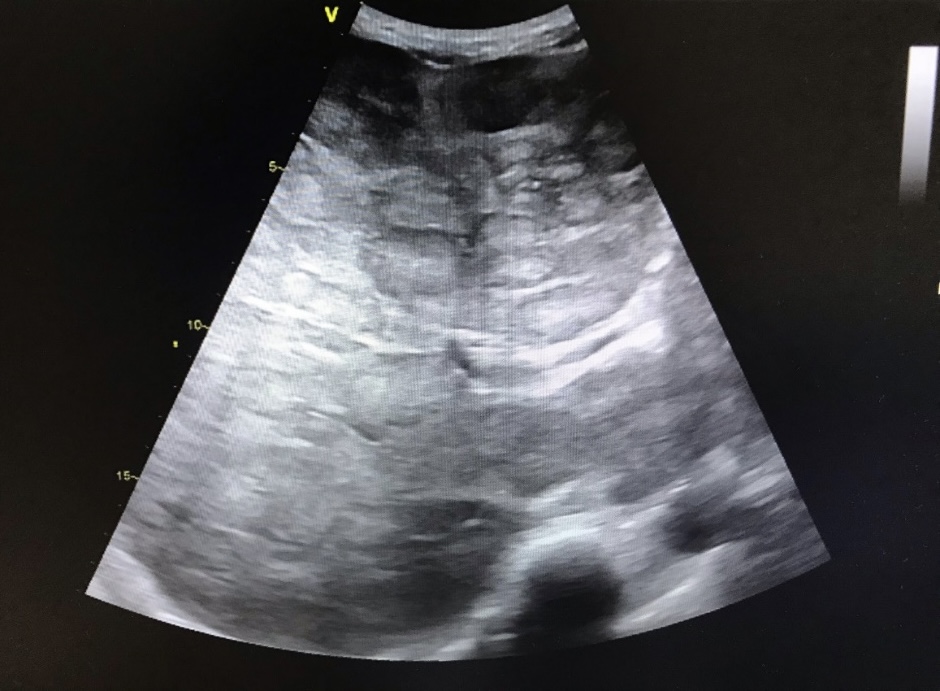

• Anamnesis, exploración física y lugar que ocupa en ella la ecografía: Hombre de 64 años que acude a consulta por astenia e hiporexia, que en los últimos 3 días se han acompañado de náuseas, vómitos y diarrea sanguinolenta. Refiere dolor en vértebras torácicas altas de un mes de evolución. En la exploración física presenta dolor a la palpación en hipocondrio derecho y hepatomegalia de 3 traveses. En consulta se realiza una ecografía abdominales-pélvica

Hallazgos ecográficos

Hepatomegalia con alteraciones difusas en toda la extensión del parénquima hepático de morfología nodular. No se observan otras alteraciones patológicas.